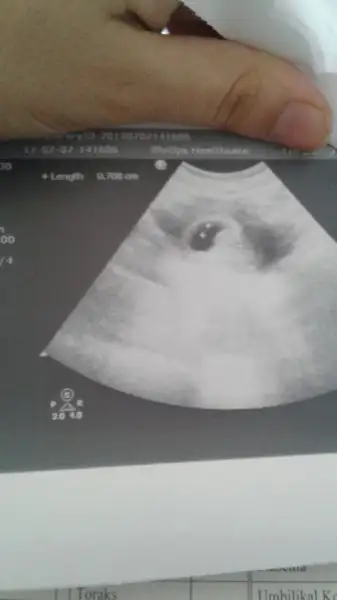

Allh razi olsun ama ne yazikki iyi haber ler alamadım pazartesi belli olack herseyEsr02 merhaba canım kaç gündür bakıyordum yazdıklarına dua ettim hep senin için insalah bebeğin seninledir diye bugün de doktora gittin inşallah iyi haberler almışsındır.. Allah yardımcın olsun dualarım seninle ve yavrunla.